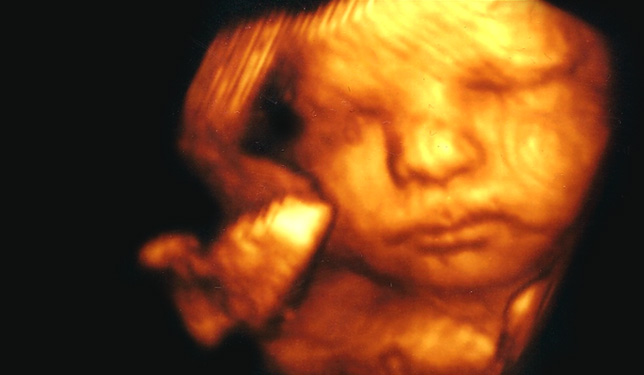

O Centro Ecográfico de Entrecampos (CEEC) tem vindo a desenvolver exames fundamentais no acompanhamento da gravidez, na avaliação ginecológica e no estudo da infertilidade.

Dedica-se principalmente à realização de ecografias, seguindo padrões de elevada qualidade, de forma a garantir a máxima fiabilidade diagnóstica.

Para conseguir estes objectivos, mantém uma colaboração regular (auditoria anual e certificação) com a Fundação de Medicina Fetal sediada em Londres, a qual é reconhecida mundialmente pelo excelente trabalho desenvolvido no estudo do feto, nas áreas médica, de investigação e de controle de qualidade.